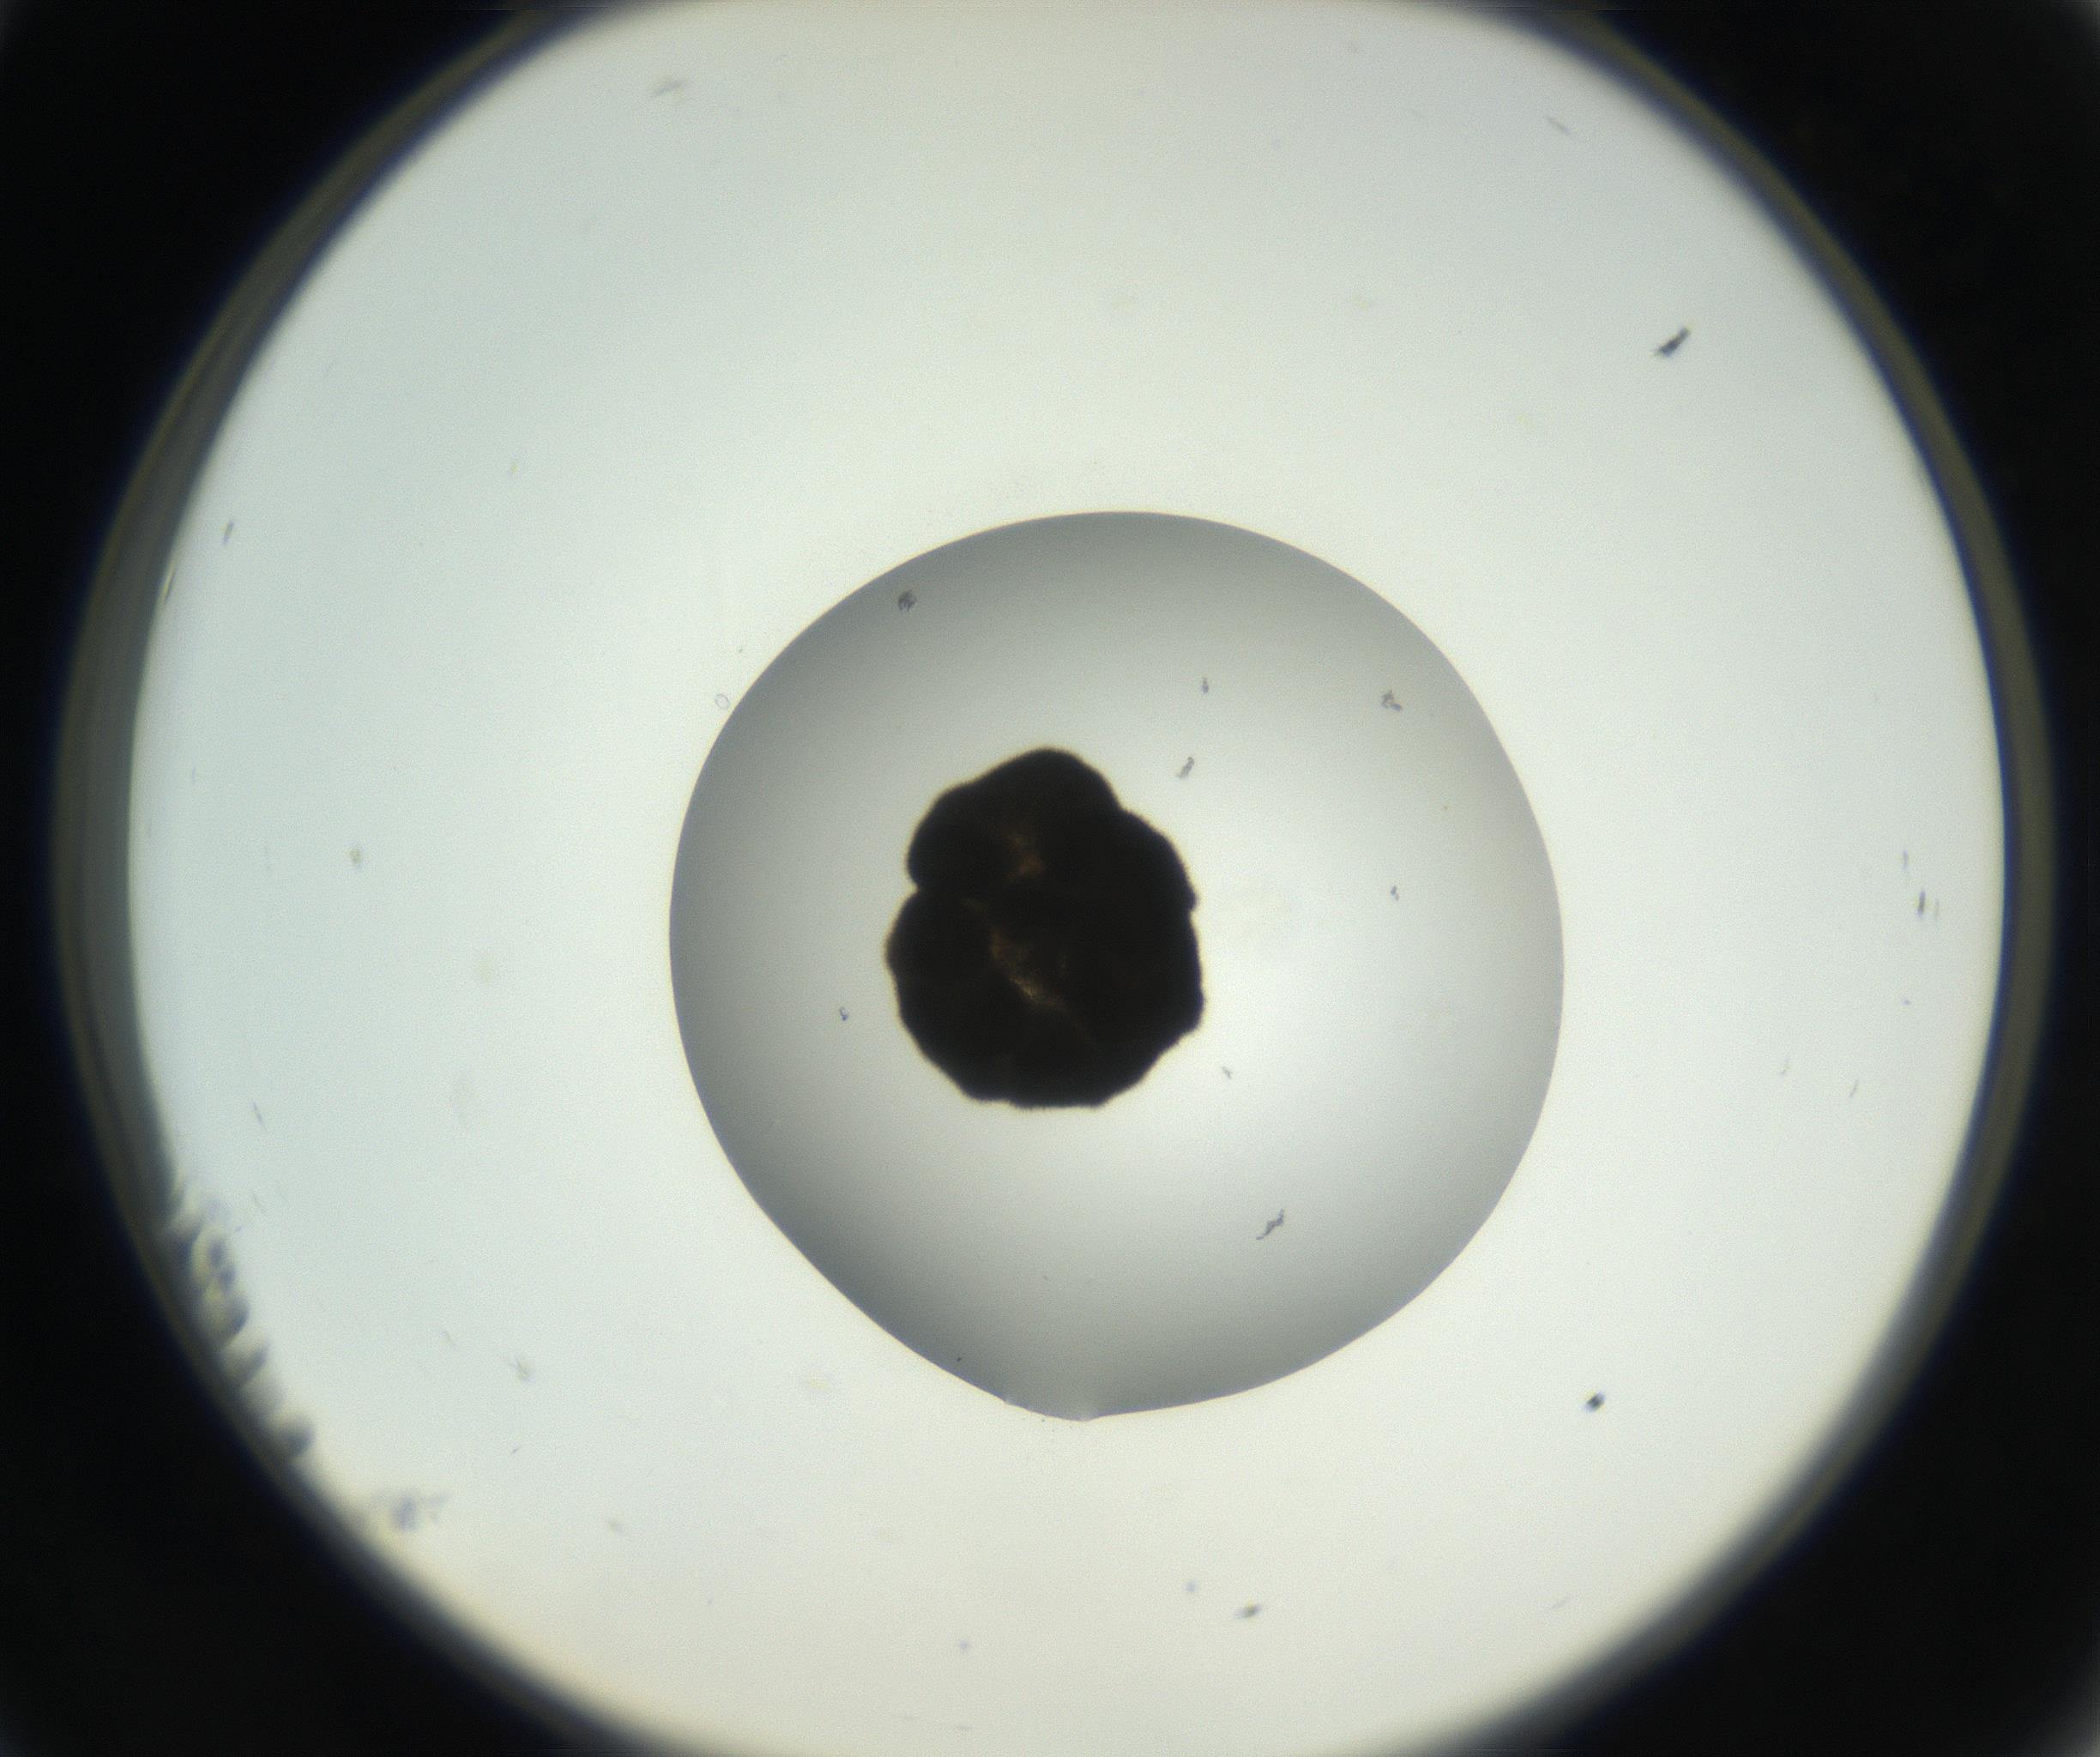

RI01_03_000_0212_Proj1_Clon1_MC_0000MC102666_004_160828_11_02_02_00_99_002_001_RAI.jpg